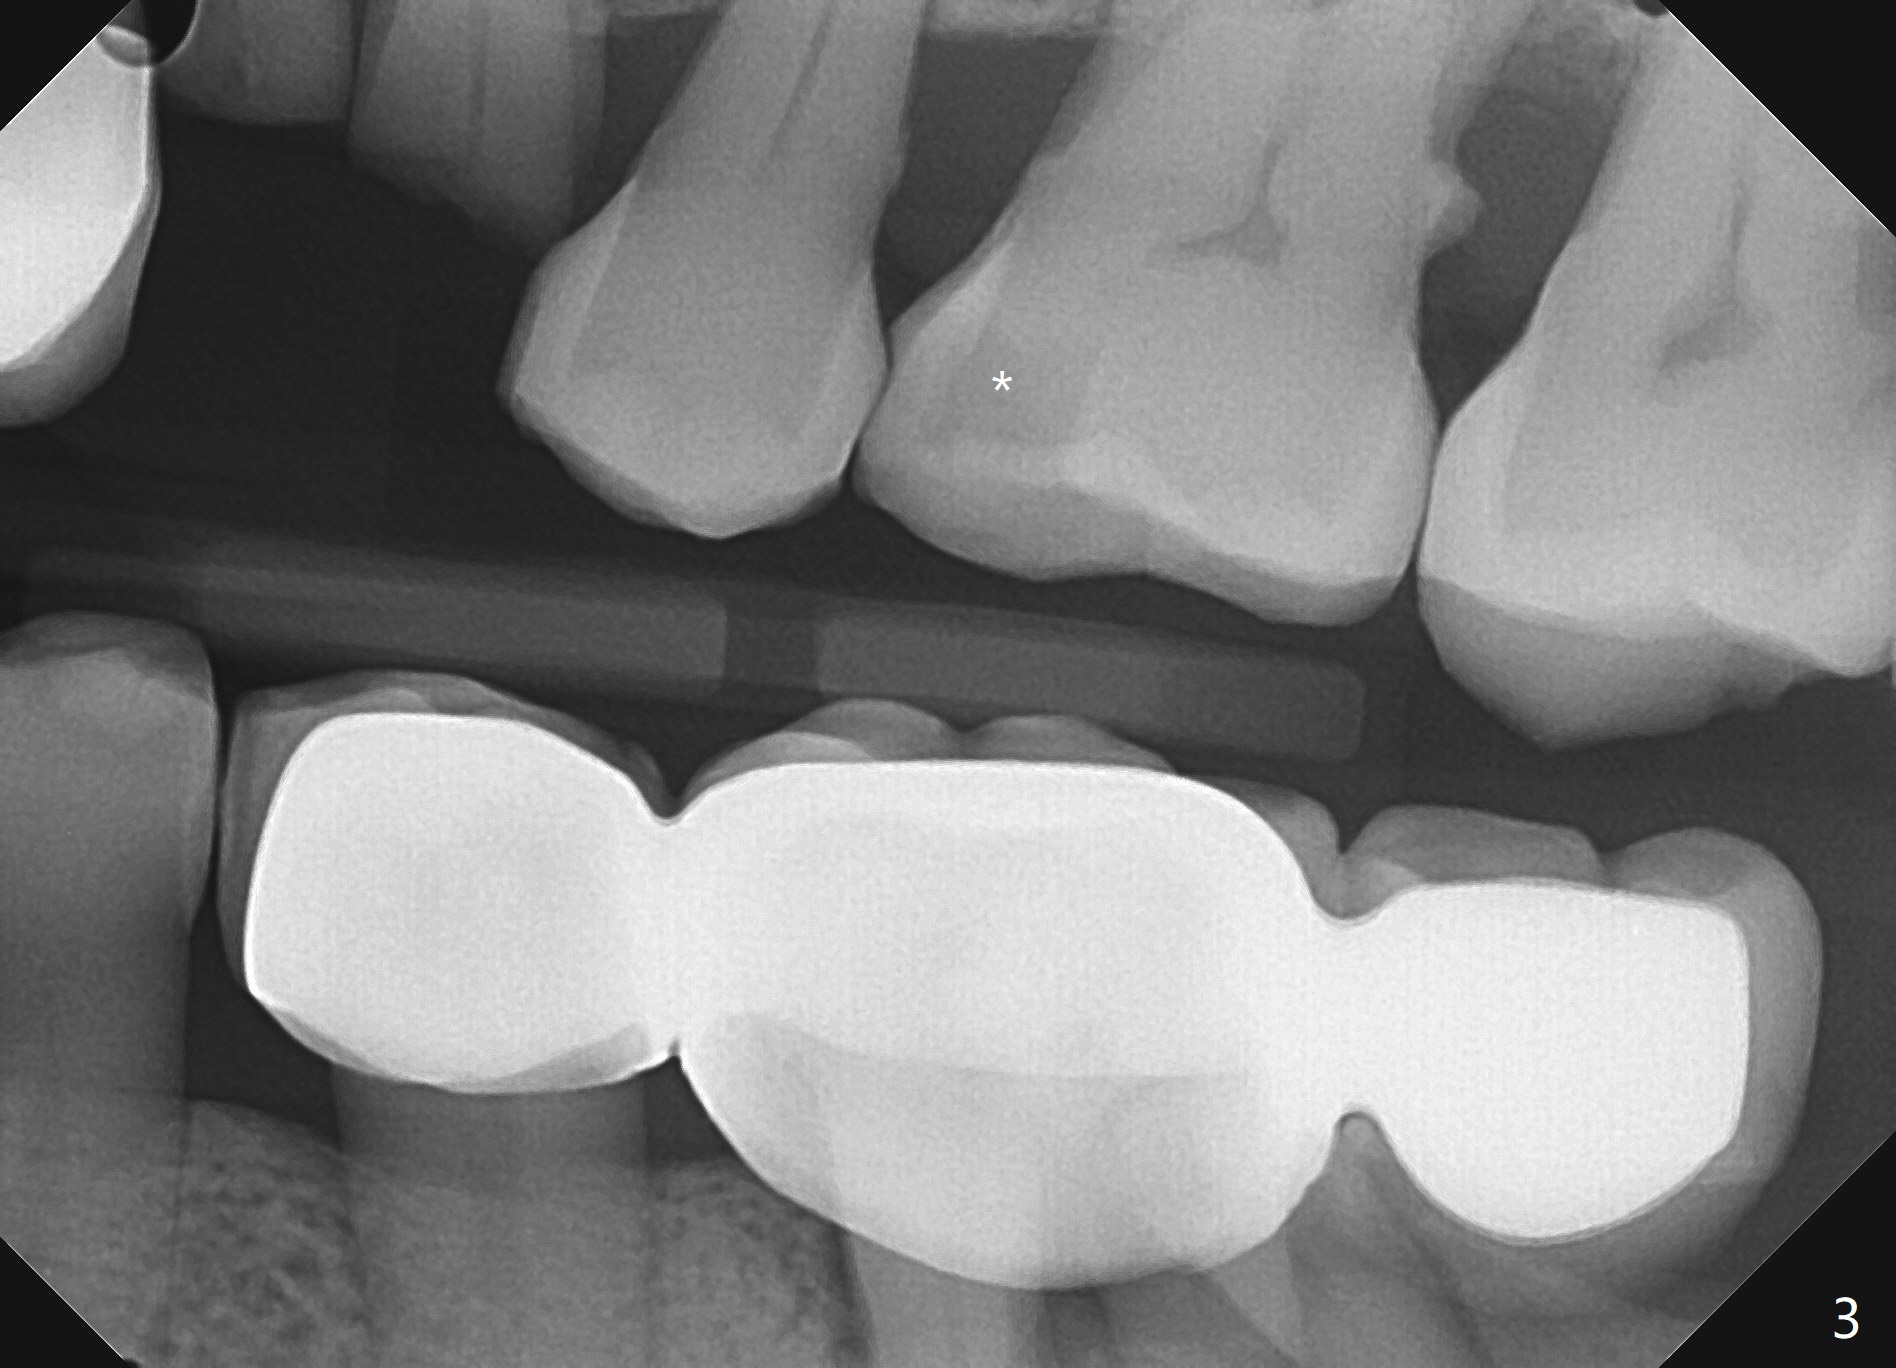

A 71 year old lady has issue with an upper bridge (#7-11, Fig.5-7). While one of the abutments (anchor teeth for FPD), #7, is "tender", the other (#11) fractures. Take Alginate impression (upper and lower) when she returns, pour models (no bubbles, 1 U, 2 L), and keep U Alginate for provisional. Section FPD at #7 and 9, take 12x9 cm CT with 2 cotton rolls and full arch impression for guide with bite registration. Prepare Endo Ice for #7 (tenderness). Tell the patient and her daughter that the lower left cantilever FPD is in bad shape, since the tooth #19 has large furca radiolucency (Fig.4 *). Next appointment should be scheduled for SRP (Fig.1-4).